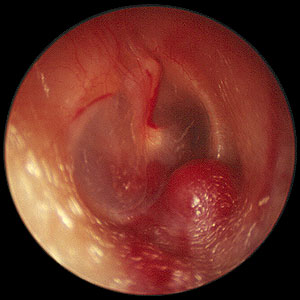

Presentation: These tumors are slow growing, with very little symptoms. The diagnosis may easily be missed. Infact the average delay between the onset of symptoms and diagnosis varied from 6 years to 15 years. The first symptoms generally follow middle ear involvement is easily overlooked. Pulsatile tinnitus and conductive deafness are the common presenting symptoms. A red mass behind an intact ear drum (rising sun sign) may also be seen. In some 30% of cases cranial nerve palsies are common. Facial nerve is affected most commonly.

Glomus jugular with Rising sun sign

Clinical features: Otoscopic examination reveals a characteristic, pulsatile, reddish-blue tumor behind the tympanic membrane that often is the beginning of more extensive findings (ie, the tip of the iceberg). When the drum is examined under a microscope will show a pulsation of the reddish mass behind the drum. On seigalisation the mass blanches. This sign is known as Brown's sign. This is pathognomonic of glomus tumor.